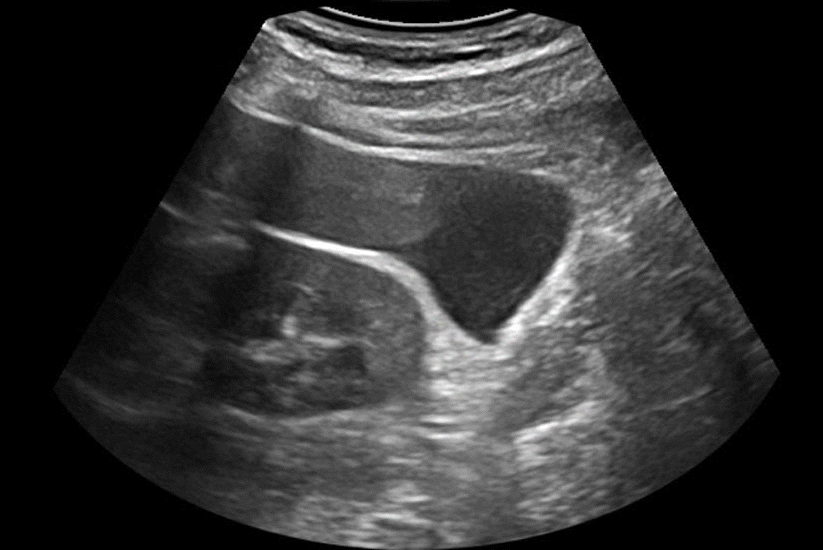

Images échographiques montrant un hémopéritoine pelvien mis en évidence sur une coupe transeverse et sagittale médiane de l'utérus ; il s'agit d'une hémorragie intra-abdominale étendue jusqu'à l'espace périhépatique (

l'espace de Morison

ou

l'espace interhépatorénal

) et due à présence, chez la patiente, d'une

grossesse extra-utérine tubaire distale hémorragique

.

Le dosage de

β-hCG

plasmatique était égal à 2400 UI/l.